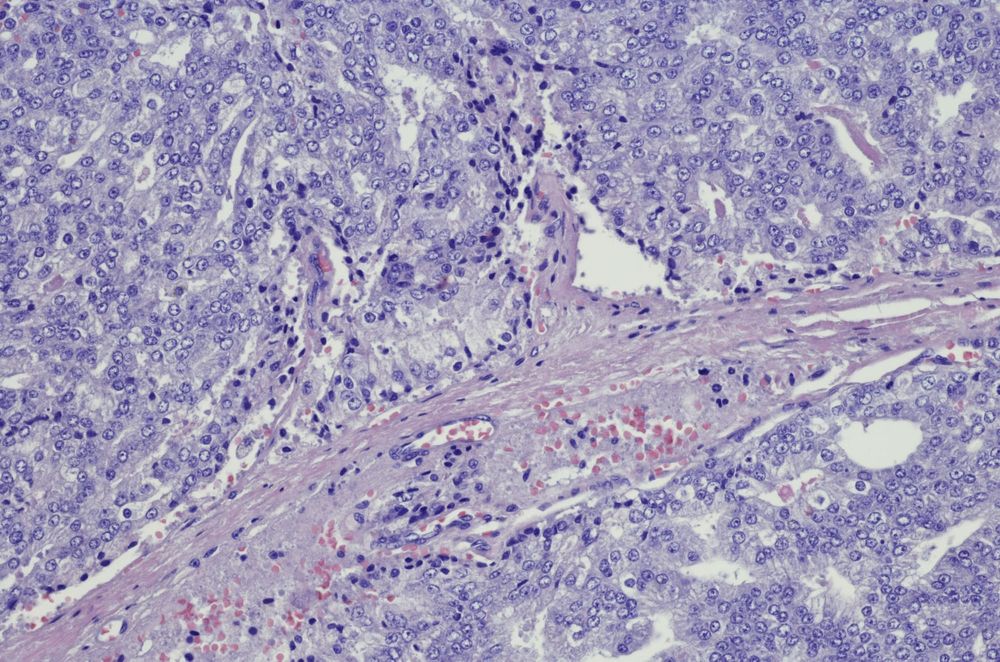

Gail gained her PhD at Monash University. As head of an internationally-recognised research team of scientists and clinicians working on prostate cancer and andrology-related projects, she’s one of Australia’s leading prostate cancer researchers, with particular interest in the biology of stromal-epithelial cell interactions in normal and tumour tissue using tissue recombination, animal and human specimens. She pioneered the use of stem cells for recombination studies combining stem cell biology with endocrinology.